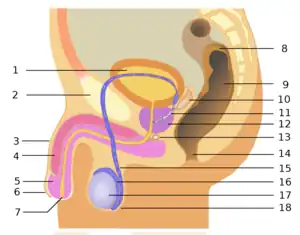

L'appareil génital masculin est l'appareil reproducteur de l'homme. Il est composé des cordons spermatiques, du scrotum, des testicules, des épididymes, des canaux déférents, des canaux éjaculateurs, des vésicules séminales, de la prostate, de l'urètre et du pénis.

Anatomie vue en perspective

Anatomie vue en perspective Anatomie vue de côté